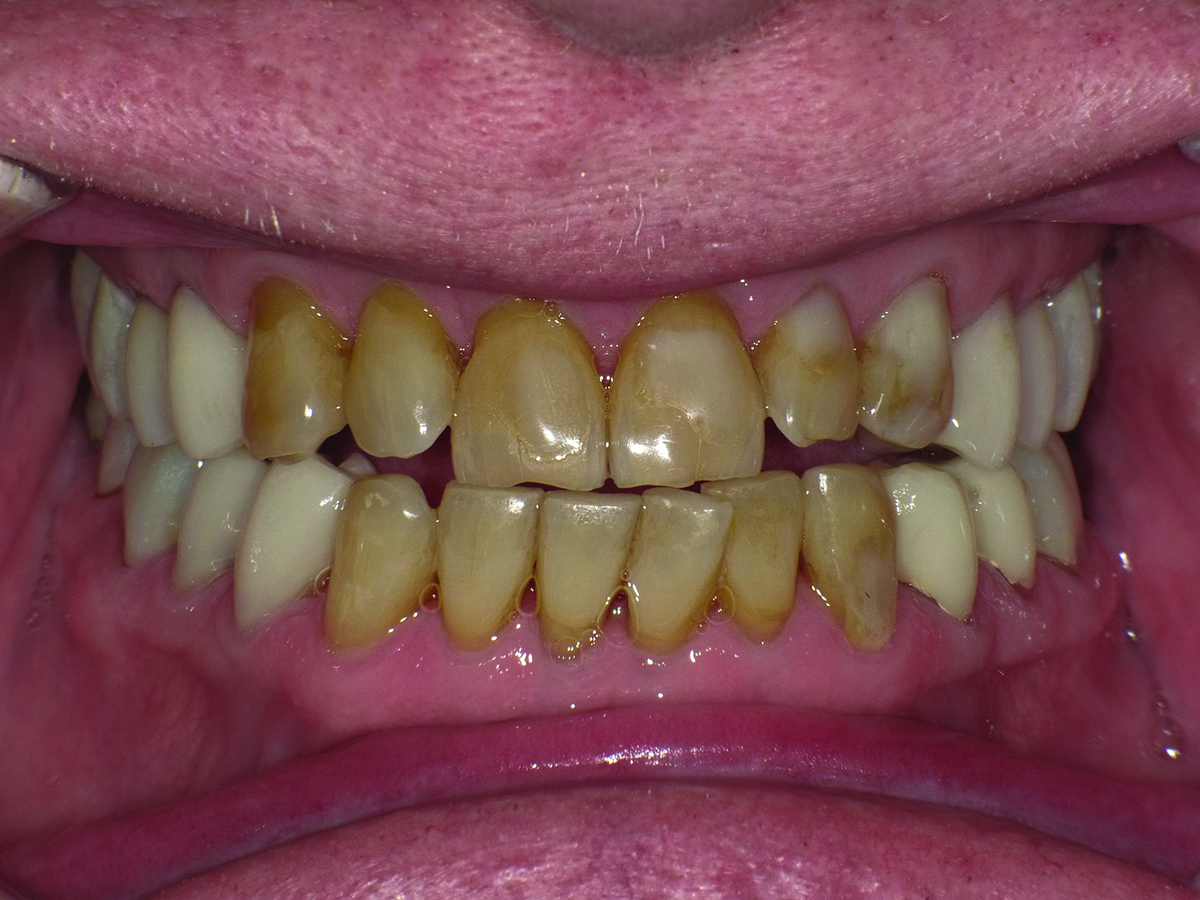

Patient’s full-face smile in 2017.

Figure 3

Dentofacial: There was no gingival display in the patient’s Duchenne smile. Teeth Nos. 7 through 10 were not visible in repose. His tooth shade was noted as A4 on the shade guide. The patient wished to have whiter teeth and feel more confident smiling.

Biomechanical: Significant tooth structure loss had occurred between 2009 and 2017 (Figure 1 through Figure 3). Severe attrition had occurred on the anterior teeth, especially tooth No. 11. Severe erosion and abrasion were present on teeth Nos. 11, 18, 20, 21, 28, 29, 31, and 32 (Fig-

ure 4). The patient had generalized sensitivity, and tooth No. 18 was painful due to deep erosion, which approached the pulp chamber. Teeth Nos. 7 and 10 had moved out of position and rotated (Figure 5). The progression of erosion over the 8-year period could also be seen radiographically and was especially noticeable on tooth